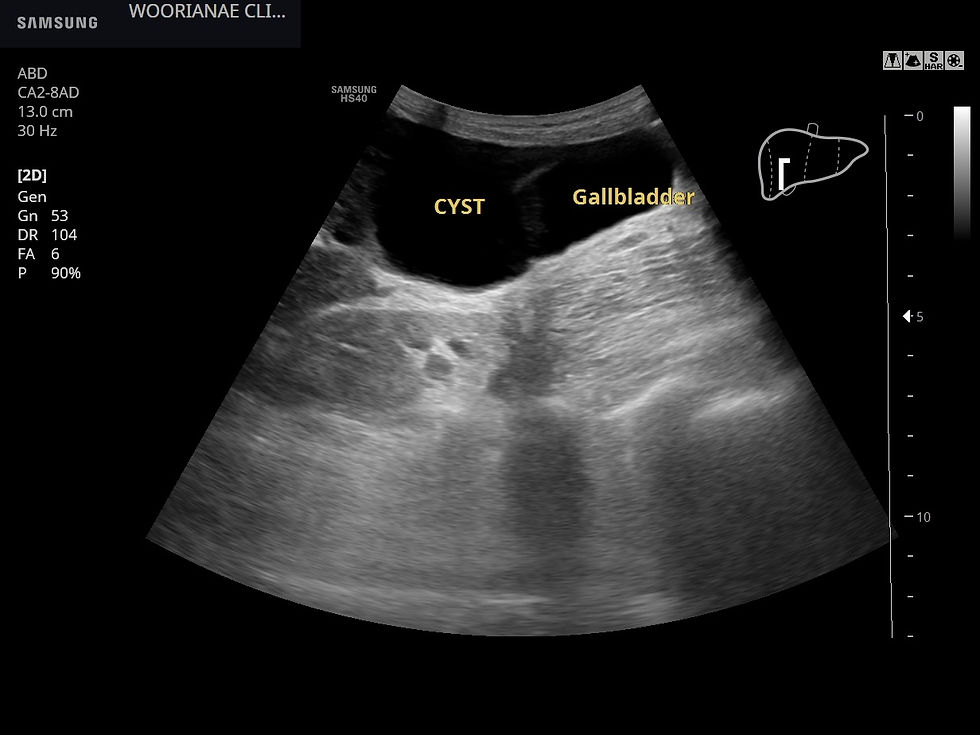

초음파 시행

우엽 5번 구역에 큰 간낭종, 이외에 4~5개의 낭종 및 고음영 종괴 (일반적으로 혈관종 소견) 가 2개 있었다.

간 아래 낭종에 의해 담낭의 구별이 어려운데 사이 공간에 위치하고 있다.

내부에 찌꺼기, debris 가 있는 낭종이 배꼽 높이까지 내려와 관찰되는데 크기는 7*7 cm 정도

췌장염 기왕력이 명확하지 않은데 pancreastic pseudocyst? 가성낭종?